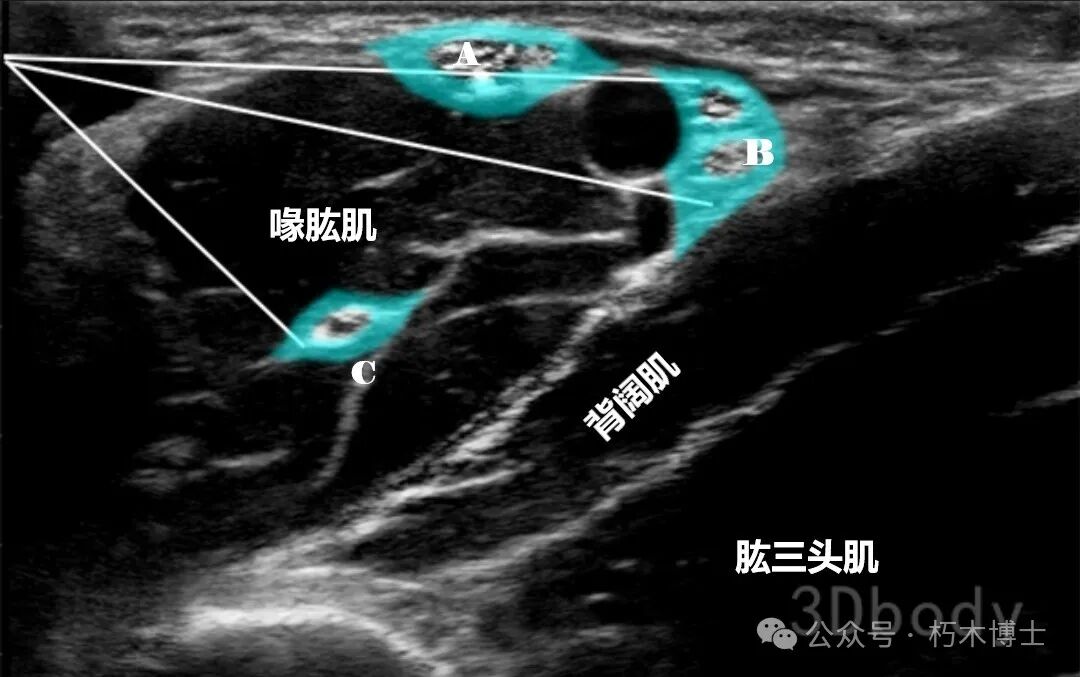

2. 操作要点: - 患者头转向对侧。 - 将探头置于内侧锁骨下窝,与锁骨平行并紧靠锁骨,识别腋动脉。 - 识别腋动脉外侧的臂丛神经束。 - 平面内技术,从外侧向内侧进针,目标在三条神经束之间,注入 15-20ml 局麻药。**四、腋路**1. 解剖:阻滞水平位于臂丛的末端。2. 适用手术:一般用于前臂和手部手术麻醉,也可用于肘部手术麻醉。3. 超声解剖图:可见搏动的腋动脉,动脉旁有腋静脉,腋动脉周围有正中神经、尺神经、桡神经和肌皮神经。

![]()

图4. A:正中神经;B:尺神经和桡神经;C:肌皮神经。浅蓝色为注射区域,白色直线为注射针。(图源:3Dbody)

4. 操作要点: - 患者头转向对侧。 - 皮肤消毒,探头平行于臂短轴方向放置,辨认腋动脉。 - 确定腋动脉后寻找正中神经、尺神经和桡神经。 - 在上臂近端和远端移动探头寻找肌皮神经。 - 确定目标结构后,平面内技术从头侧向腋动脉后方进针,先用小剂量局麻药或其他注射液进行液体分离神经血管组织。 - 局麻药先注射到腋动脉下方,然后针尖退回皮下,调整方向向正中神经和尺神经注射,最后将针退回肱二头肌内,朝向肌皮神经注射。 - 动脉周围局麻药的完全包绕是成功阻滞的关键,常需两点或三点注射,同时要另外注射以阻滞肌皮神经。